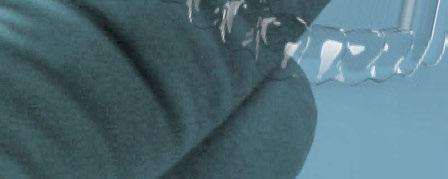

A continuación, para la planificación de los implantes dentales y el diseño de la férula de cirugía guiada se usó la plataforma digital RealGUIDE®. Para ello se realizó el matching, por un lado, del archivo STL del encerado digital; y, por otro, del archivo 3D. De esta manera, se pudo analizar el tejido óseo residual apical a cada diente y la posición de la raíz respecto a las corticales vestibular y palatina. También se estudió la relación de los contornos óseos con los tejidos blandos y con la posición final de los márgenes cervicales de la restauración protésica, pudiendo así planificar la posición 3D correcta de los implantes. En esta primera fase se diseñó una férula quirúrgica para la elevación de seno bilateral a partir del software RealGUIDE™, que nos sirvió de guía para el diseño de las ventanas de acceso. Esta férula se imprimió con la impresora 3D Formlabs® (Figura 7)

3. Fase quirúrgica final

A los 6 meses de cicatrización, se realizó un nuevo CBCT, obteniendo un nuevo archivo DICOM que alineamos con el STL del encerado. De esta manera, se planificó la posición de los implantes a 4 mm del margen de la restauración final y se diseñó y confeccionó la férula de cirugía guiada dentosoportada en 12-13 y 22-23, la cual imprimimos con la impresora 3D Formlabs®. El provisional

de carga inmediata lo diseñamos con el programa de diseño 3D Exocad® a partir del encerado y se imprimió también en clínica con la misma impresora 3D (Figuras 14-16).